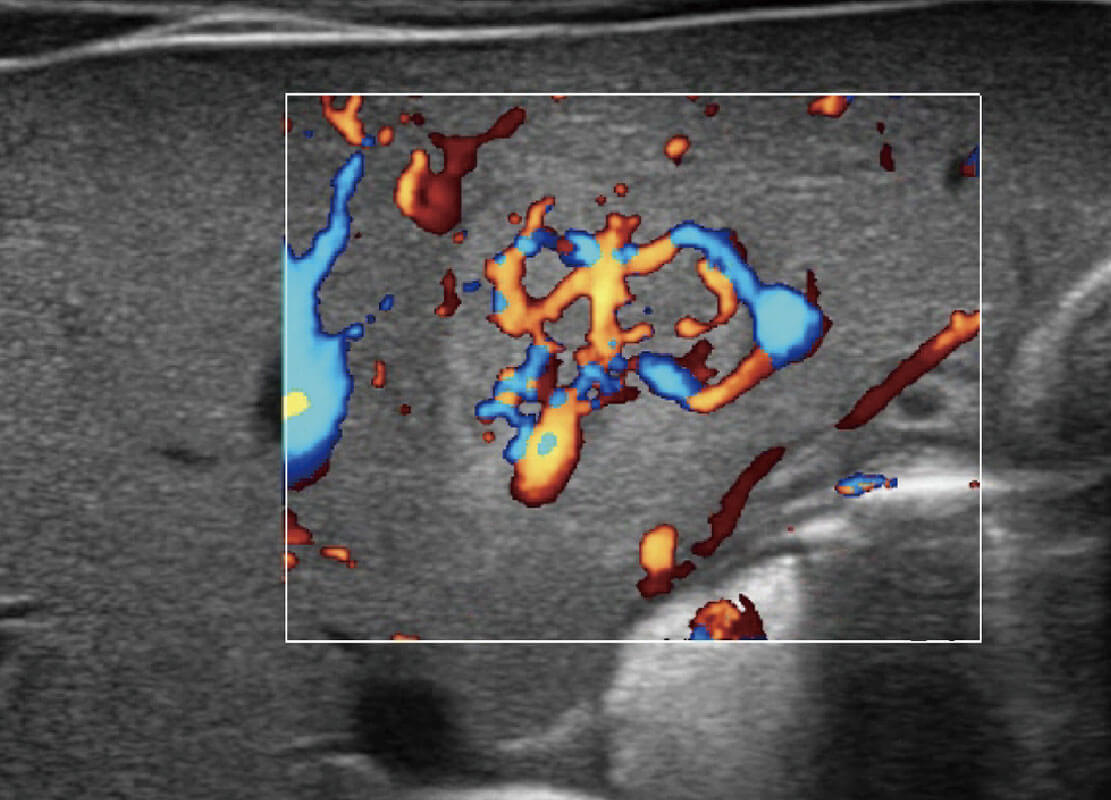

胎儿体循环

四腔心血流